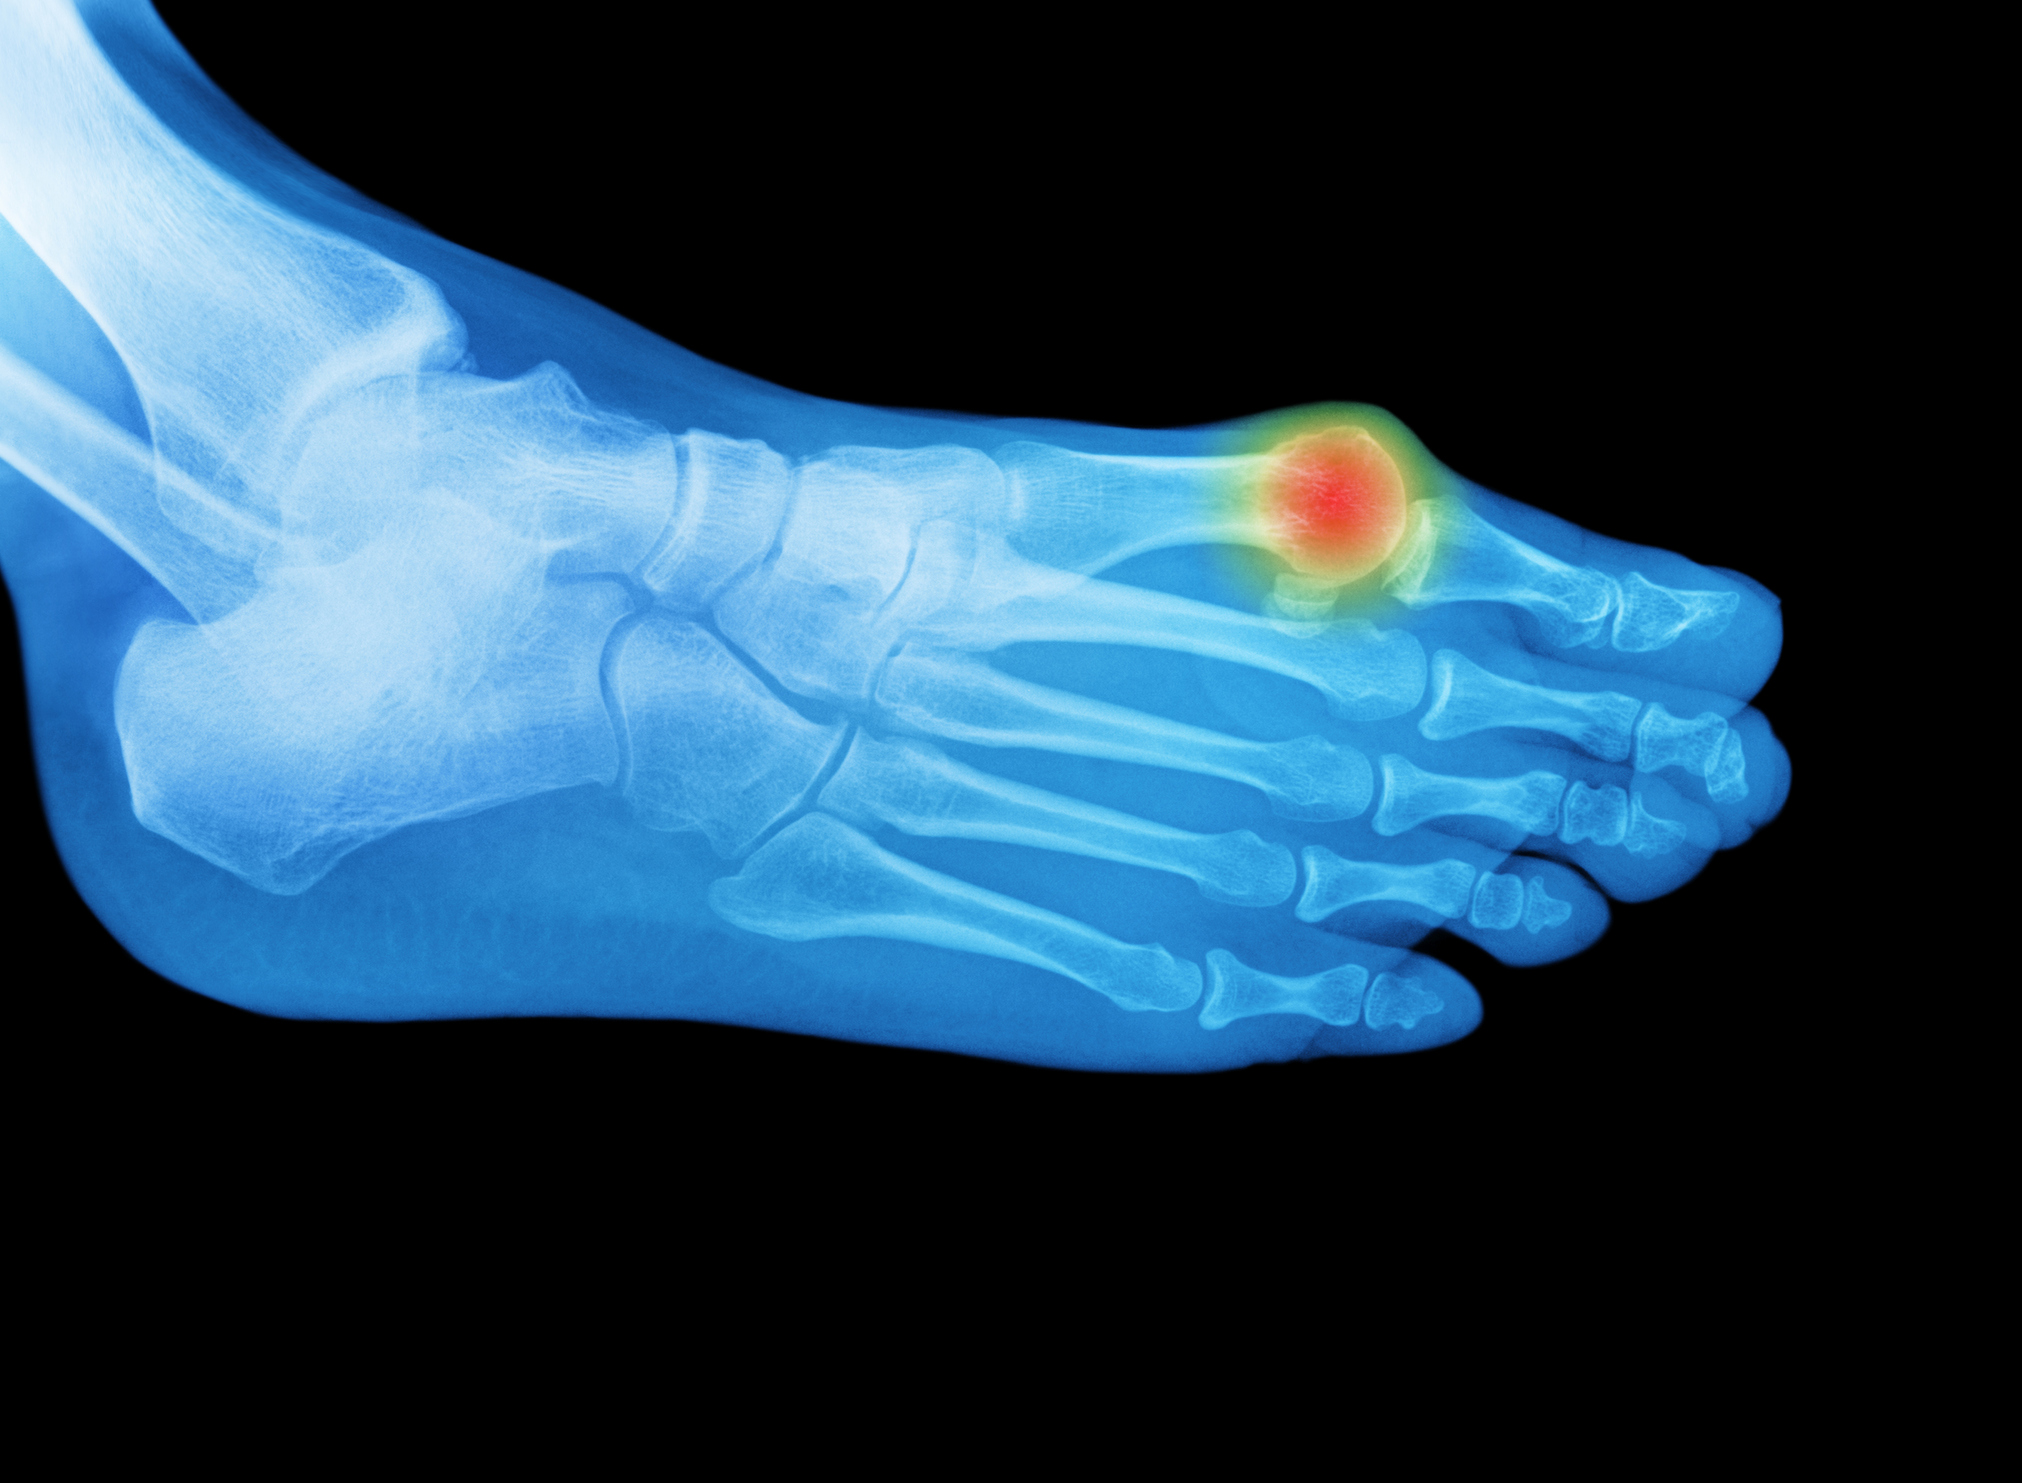

Qu'est-ce qu'une crise de goutte ?